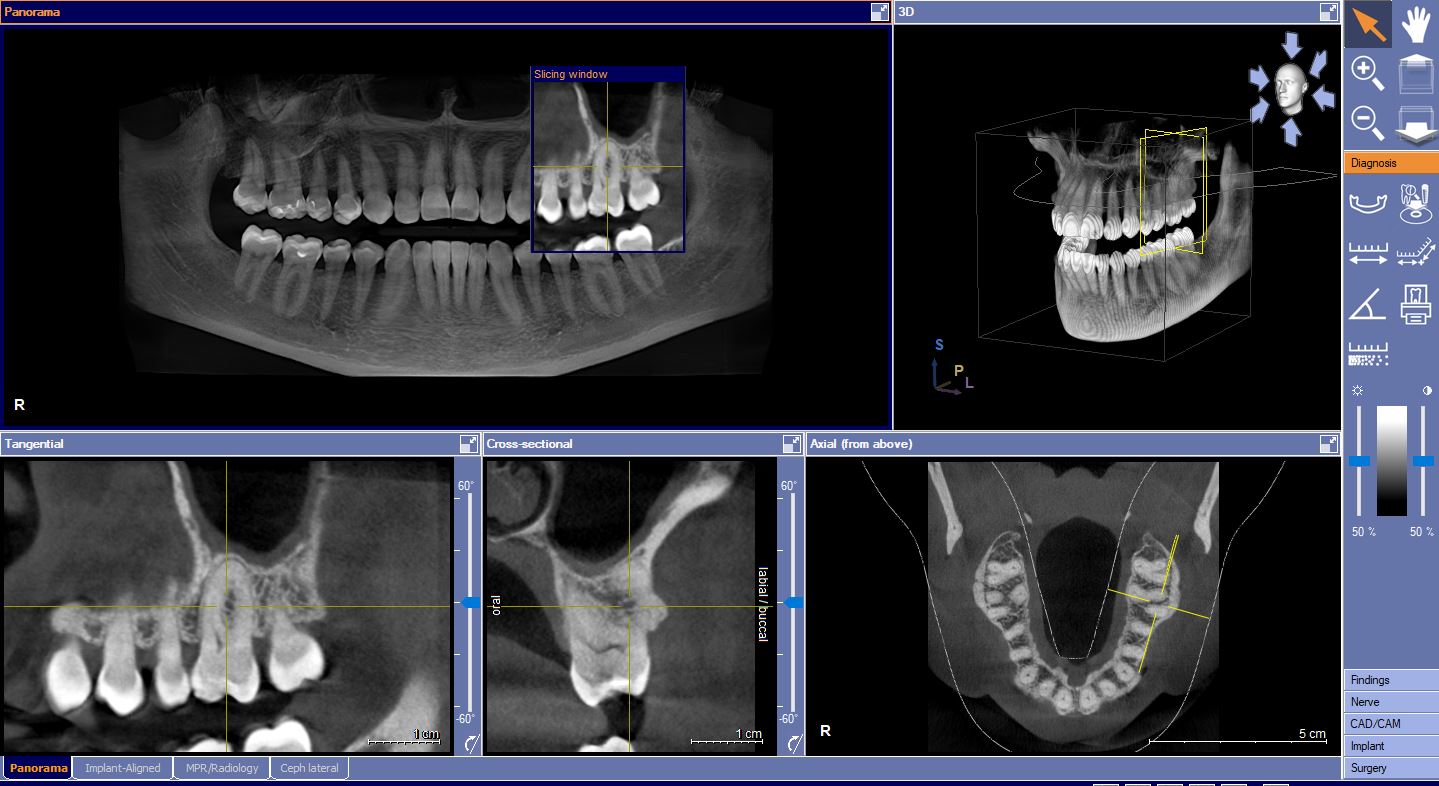

7. Rendgensko snimanje zubi

- pojedinačne intraoralne snimke

- panoramsko snimanje zubi

- 3D snimanje zuba i čeljusti - CBCT

13. CBCT - 3D snimanje zuba i čeljusti

CBCT zuba (eng. Cone Beam Computed Tomography) ili dentalna konusna kompjutorizirana tomografija je vrsta trodimenzionalne digitalne rendgenske snimke pojedinačnog zuba, zubne kosti i okolnih tkiva zuba. Ova vrsta snimke pomaže kod planiranja operativnih zahvata i implantacije.